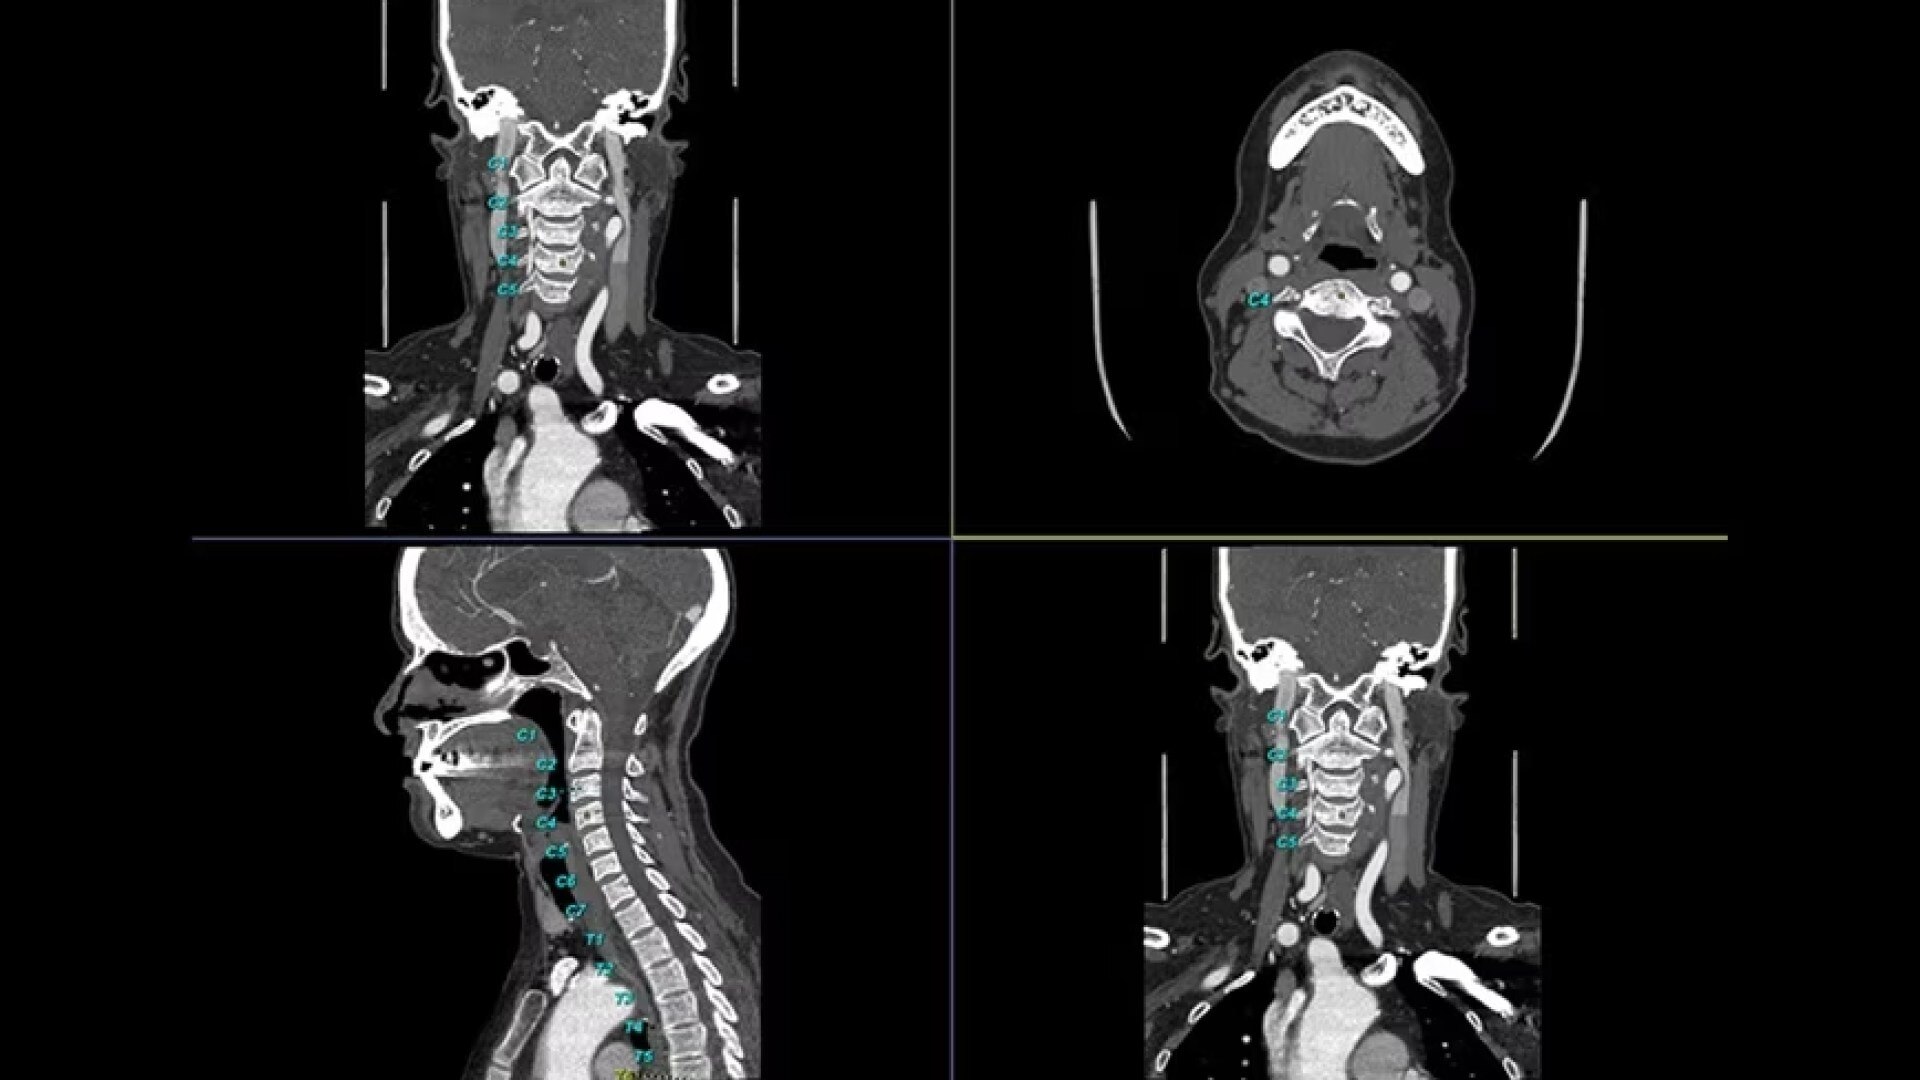

Automated spine identification and labelling.

>90% labeling accuracy based on Deep learning algorithm trained on global datasets acquired with a broad range of acquisition parameters.

• Automated spine labeling

• Load multiple series and vertebrae labeling will propagate to the different volumes